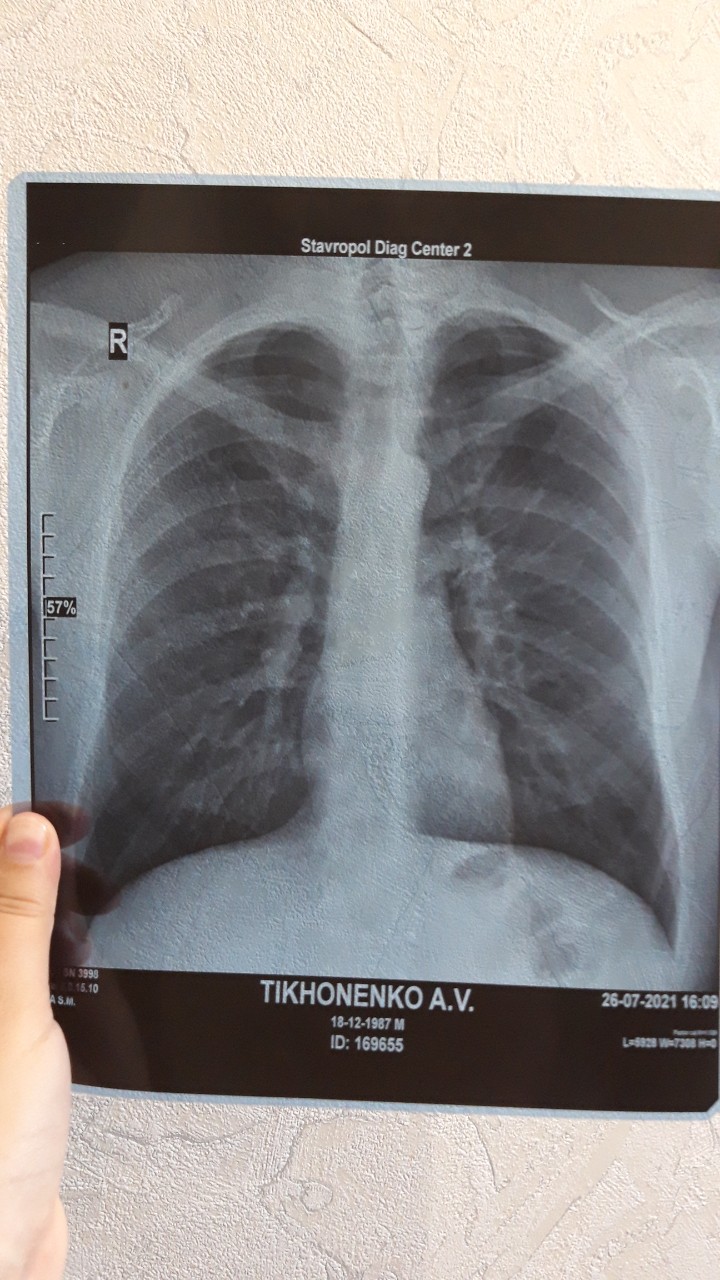

Рентгеновские технологии: усиленные экраны 35x35